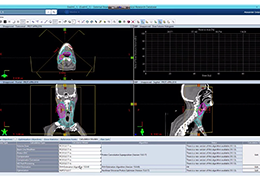

单屏工作效率与安全

ImageView 软件平台旨在通过提供以下功能,大幅提高影像效率和安全性:

所有 Carestream 影像采集产品通用的用户界面

减少屏幕切换,节省时间并增强工作流程

内置“安全设计”元素,提供入侵保护和防护